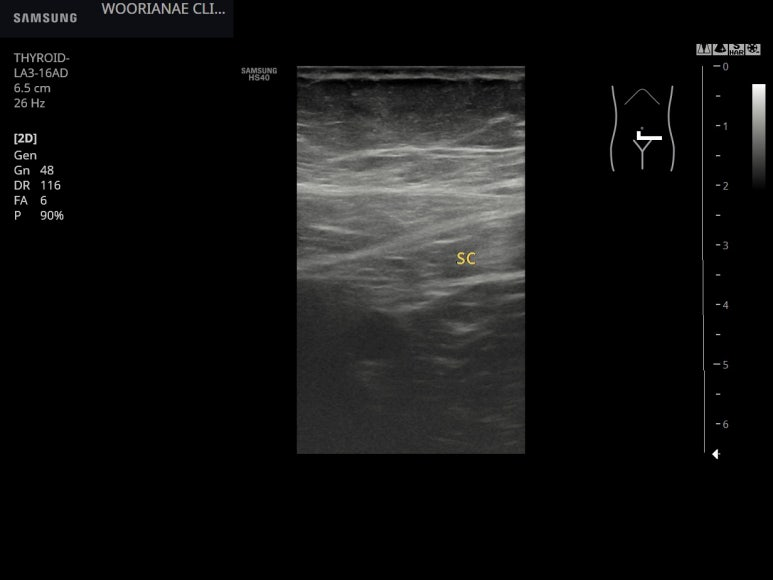

원위부 하행결장의 확인

주행방향의 에스결장

단면의 에스결장, 대장벽/근육층을 확인할 수 있다. 주변에 염증성 지방변화나 게실은 보이지 않는다.

최대한 원위부까지...

게실염은 배제하고